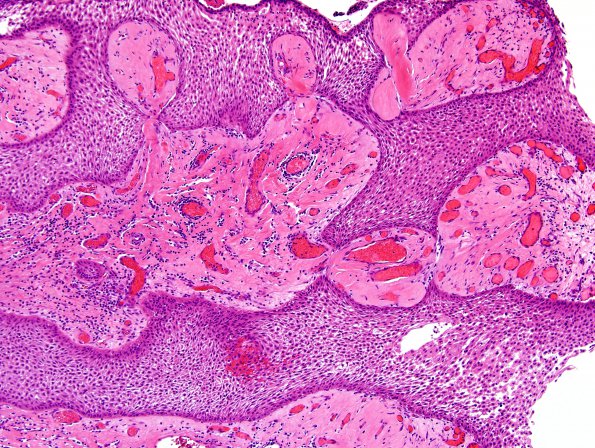

Washington University Experience | NEOPLASM (SELLAR) | Craniopharyngioma, papillary | 1B3 Craniopharyngioma, papillary (Case 1) H&E 10X 1

Sections of the resected suprasellar mass show maturing squamous epithelium surrounding fibrovascular cores with chronic inflammation and hyalinization. The epithelium lacks surface maturation.